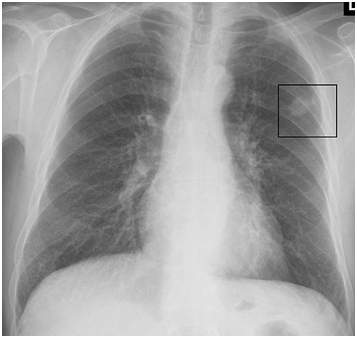

Radiografija pluća - Ovo je jednostavan i brz test koji

može da pokaže lokalizaciju, veličinu i poziciju tumora. Ponekad je ovo

nedovoljan pregled jer cesto ne dobijamo dovoljno informacija o tumoru

a ne tako retko možemo dobiti normalan nalaz koji ukoliko su prisutni

simptomi zahteva dodatne dijagnostičke postupke.